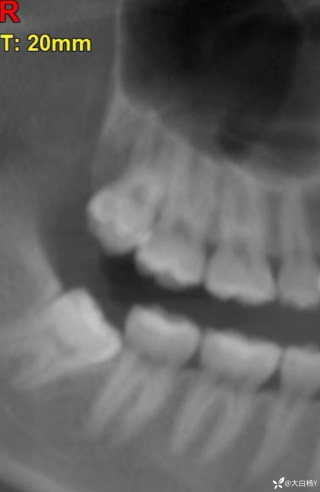

西地兰vip普外科医师

文/西地兰 特别声明:所有观点仅代表个人言论 特别声明:与当事双方均无利益相关 山东男孩,目前全网沸沸扬扬,看过一些观点,直言不讳地说,大多偏颇。要么一股脑地指责医方的全责,甚至有说千万别在县医院看病。要么又为医方无休止的遮羞,认为这样的手术在县医院做下来已经非常了不起。而我想到的是,以后面临类似的病例,我们怎么办?那么我们不如来一次专业的病案讨论。既然是事后讨论,难免有事后诸葛亮的感觉,但是假如下一次,同行们遭遇这样的病例,如何处置?这是医疗行业所面临的问题。希望我整理的这些思路和相关病例,对同行们有所帮助!就目前的资讯外界不足以判断是否需要急诊,如果需要急诊,那么只能根据术中所见进行处理,

目前知道的消息,第一,术前发现一个血肿,然后做增强CT发现一个占位,没说血肿与肿瘤的关系,术后病理没有描述肿瘤出现破裂出血,大概率就一个小血肿,我就不明白当地主任凭哪个指针去给这小孩开急诊刀的?哪个指南告诉他需要急诊开?第二,诊断不明确他想的不是进一步检查,一边观察一边进一步查,他反而选择腹腔镜探查,这个探查的指针在哪?第三,腹腔一个血肿,没有活动性出血,没有血压心率出现问题,为什么要开腹进去碰它?不能等血肿吸收再明确肿瘤性质吗?第四,1点进腹,3点病理结果出来,按这个时间还算顺利,应该还没出事,孩子还算平稳,病理是低度恶性,切了就治愈,他一年能开几台这手术,就敢继续做,拿孩子练手。第五,后面

2023年10月26日,来自山东菏泽市成武县的小烨和他家人的命运被彻底改变了。这个原本阳光、可爱的小男孩在一次意外被撞击后,在医院检查出了腹腔内存在肿瘤,并在手术中被切除了包括十二指肠、胰腺、大部分胃和小肠等多个器官。此后便无法再像正常人一样吃饭、喝水,活着要靠长期静脉注射营养液。一份2024年12月由第三方机构出具的司法鉴定意见书显示,当时给小烨做手术的成武县人民医院在该医疗行为中存在过错,与小烨的损害后果之间存在因果关系,建议医疗过错在损害后果中的原因力大小为同等原因。此外,另一份由成武县卫生健康局在2025年9月28日发出的书面答复中显示,成武县人民医院存在24小时内未完成病历;手术知情

豫刀匠秦 回复

医疗无小事,更何况牵涉到孩子,局部获益要让位于整体生存获益,SPT目前划为低度恶性,如果小于3cm可以局部切除,如果大于3cm,在主胰管附近,可以保十二指肠的胰头切除,当然保十二指肠还是要到大中心去,不过SPT应该也没有这么急切,不了解当时情况,无法置评,只能说术前评估有些草率了,当然有可能该县医院技术确实比较强,不过TPN,应该是损伤了SMA,或者SMV大出血缝闭了,不过SMV能修也能接,如果是SMB按理说不至于,只能说一句艺高人胆大!何况儿童手术,当慎之又慎!当下环境,窃以为病不好慎做,病人不好慎做,病人家属不好慎做!救命手术,下台为主!非救命手术,预后为首!炫技无用,又没人给你点赞加薪!